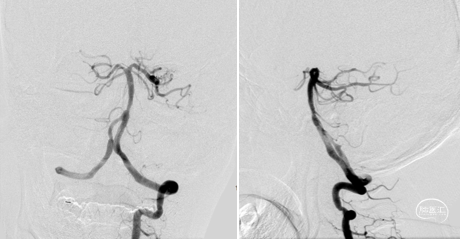

抽吸再通后造影,近端残余明显狭窄且局部毛糙,拟支架成型。

3.0*8 mm球扩支架,小压力,减少穿支损伤。

支架后造影

最后造影